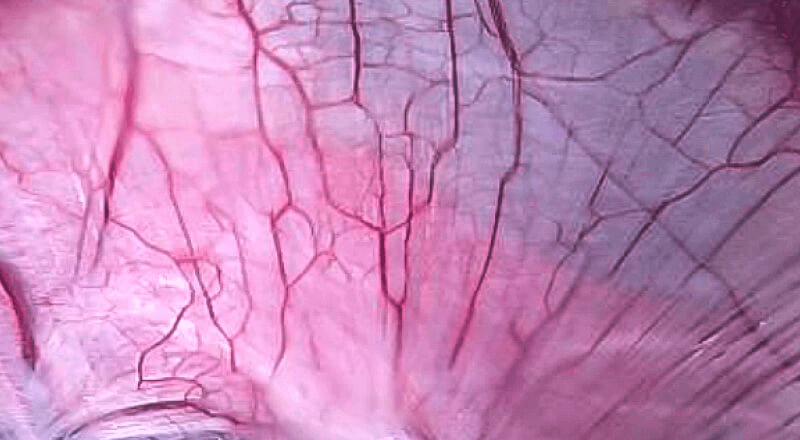

VIST光电复合染色成像技术

是一种基于血红蛋白对不同波长光吸收系数不同的原理而设计的智能染色成像系统,兼有电子染色和光学染色功能,能够凸显粘膜血管结构,有助于病灶部位识别和诊断,为临床医生术中判断提供参考信息。

• 400 500 600 700(nm)

血管对比度分布光谱曲线

• VIST光谱

多光谱输出,增强粘膜血管对比显示